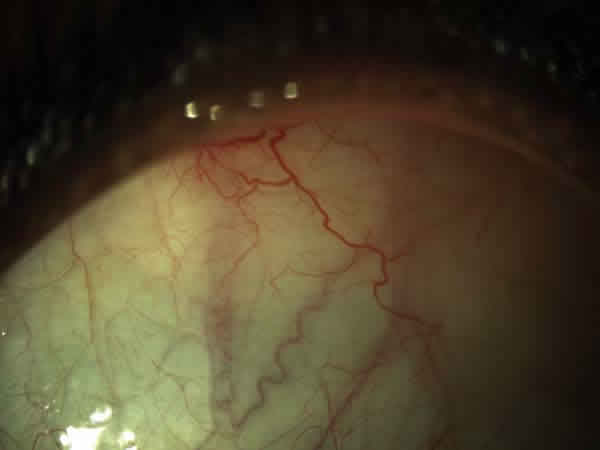

En la exploración oftalmológica la agudeza visual mejor corregida (AVMC) era de 0,6 en ambos ojos (AO). Por biomicroscopía anterior se apreciaba muy leve tortuosidad de los vasos conjuntivales, sin atrofia iridiana (fig. 1). La tonometría era de 16 mmHg. AO La funduscopía de ojo derecho (OD) mostraba oclusiones vasculares en la periferia 360 grados, con terminación muy abrupta de los mismos, telangiectasias, anastomosis arteriovenosas, zonas de no perfusión capilar, vasos hialinizados (fig. 2). El ojo izquierdo (OI) presentaba además de las lesiones descritas en el OD, neovasos muy llamativo en «abanico» en la zona temporal superior y blanco sin presión en la periferia nasal (fig. 3).

Fig. 1: Tortuosidad de los vasos conjuntivales.